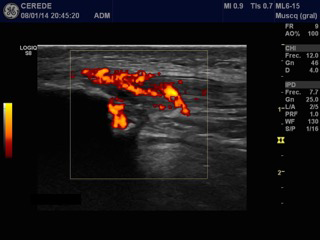

Figure 1 Ultrasound image with power Doppler. Longitudinal view of a Patellar neovascular tendinopathy, with thickening of the tendon and hipoecoic image.

Structural findings of collagen degeneration and angiofibroblastic neoplasia have been well described and are now referred to as "neovascular tendinosis." The presence of neovascularization has been theorized to cause pain in patients with tendinopathy.2 Recent studies have examined the role of neo-vessels and neo-innervations on chronic tendon pain and dysfunction, and interventions targeting this process have reported favorable outcomes in RPT (Figure 1-4).3